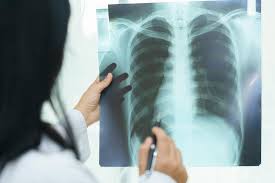

How Do I Know If I Have A Collapsed Lung - Examination of the chest by listening with a stethoscope and tapping techniques can suggest pneumothorax.

Examination of the chest by listening with a stethoscope and tapping techniques can suggest pneumothorax. Sharp and stabbing pain on one side of the chest if that pain increases as you try to inhale bluing skin, especially at the lips, indicating low oxygen absorption See full list on emedicinehealth.com Some symptoms of a collapsed lung are: You may also have trouble breathing or shortness of breath. If you have signs or symptoms of a collapsed lung, such as chest pain or trouble breathing, get medical care right away. See a doctor for any type of chest pain or suspected pneumothorax. If blood is coughed up (hemoptysis) after chest trauma or rib injury, this can be a sign of a more serious condition and should be treated by a doctor. See full list on emedicinehealth.com Causes of collapsed lung include trauma to the chest cavity (fractured rib, penetrating trauma from a bullet, knife, or other sharp object), cigarette smoking, drug abuse, and certain lung diseases. Here, the doctors will be able to see if your lung has collapsed and will be able to give you appropriate treatment. A collapsed lung is rare, but it can be serious. The penetrating trauma may be caused by a stab wound from a sharp object, gunshot wound, and blunt trauma that breaks a rib that punctures into the lung space.